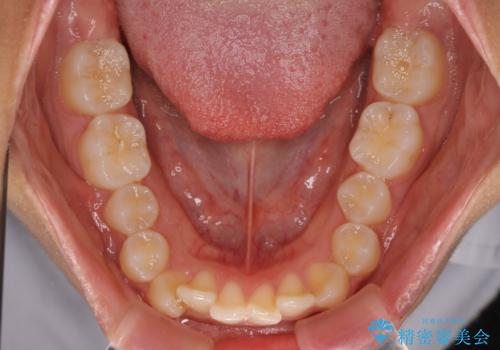

- 上下前歯の叢生を気にして来院された患者様です。

インビザラインでの治療を希望されていて、デコボコの程度が中等度であり、安価なパッケージにて対応可能と判断されたため、インビザライン・モデレートを用いて矯正治療を行うこととしました。